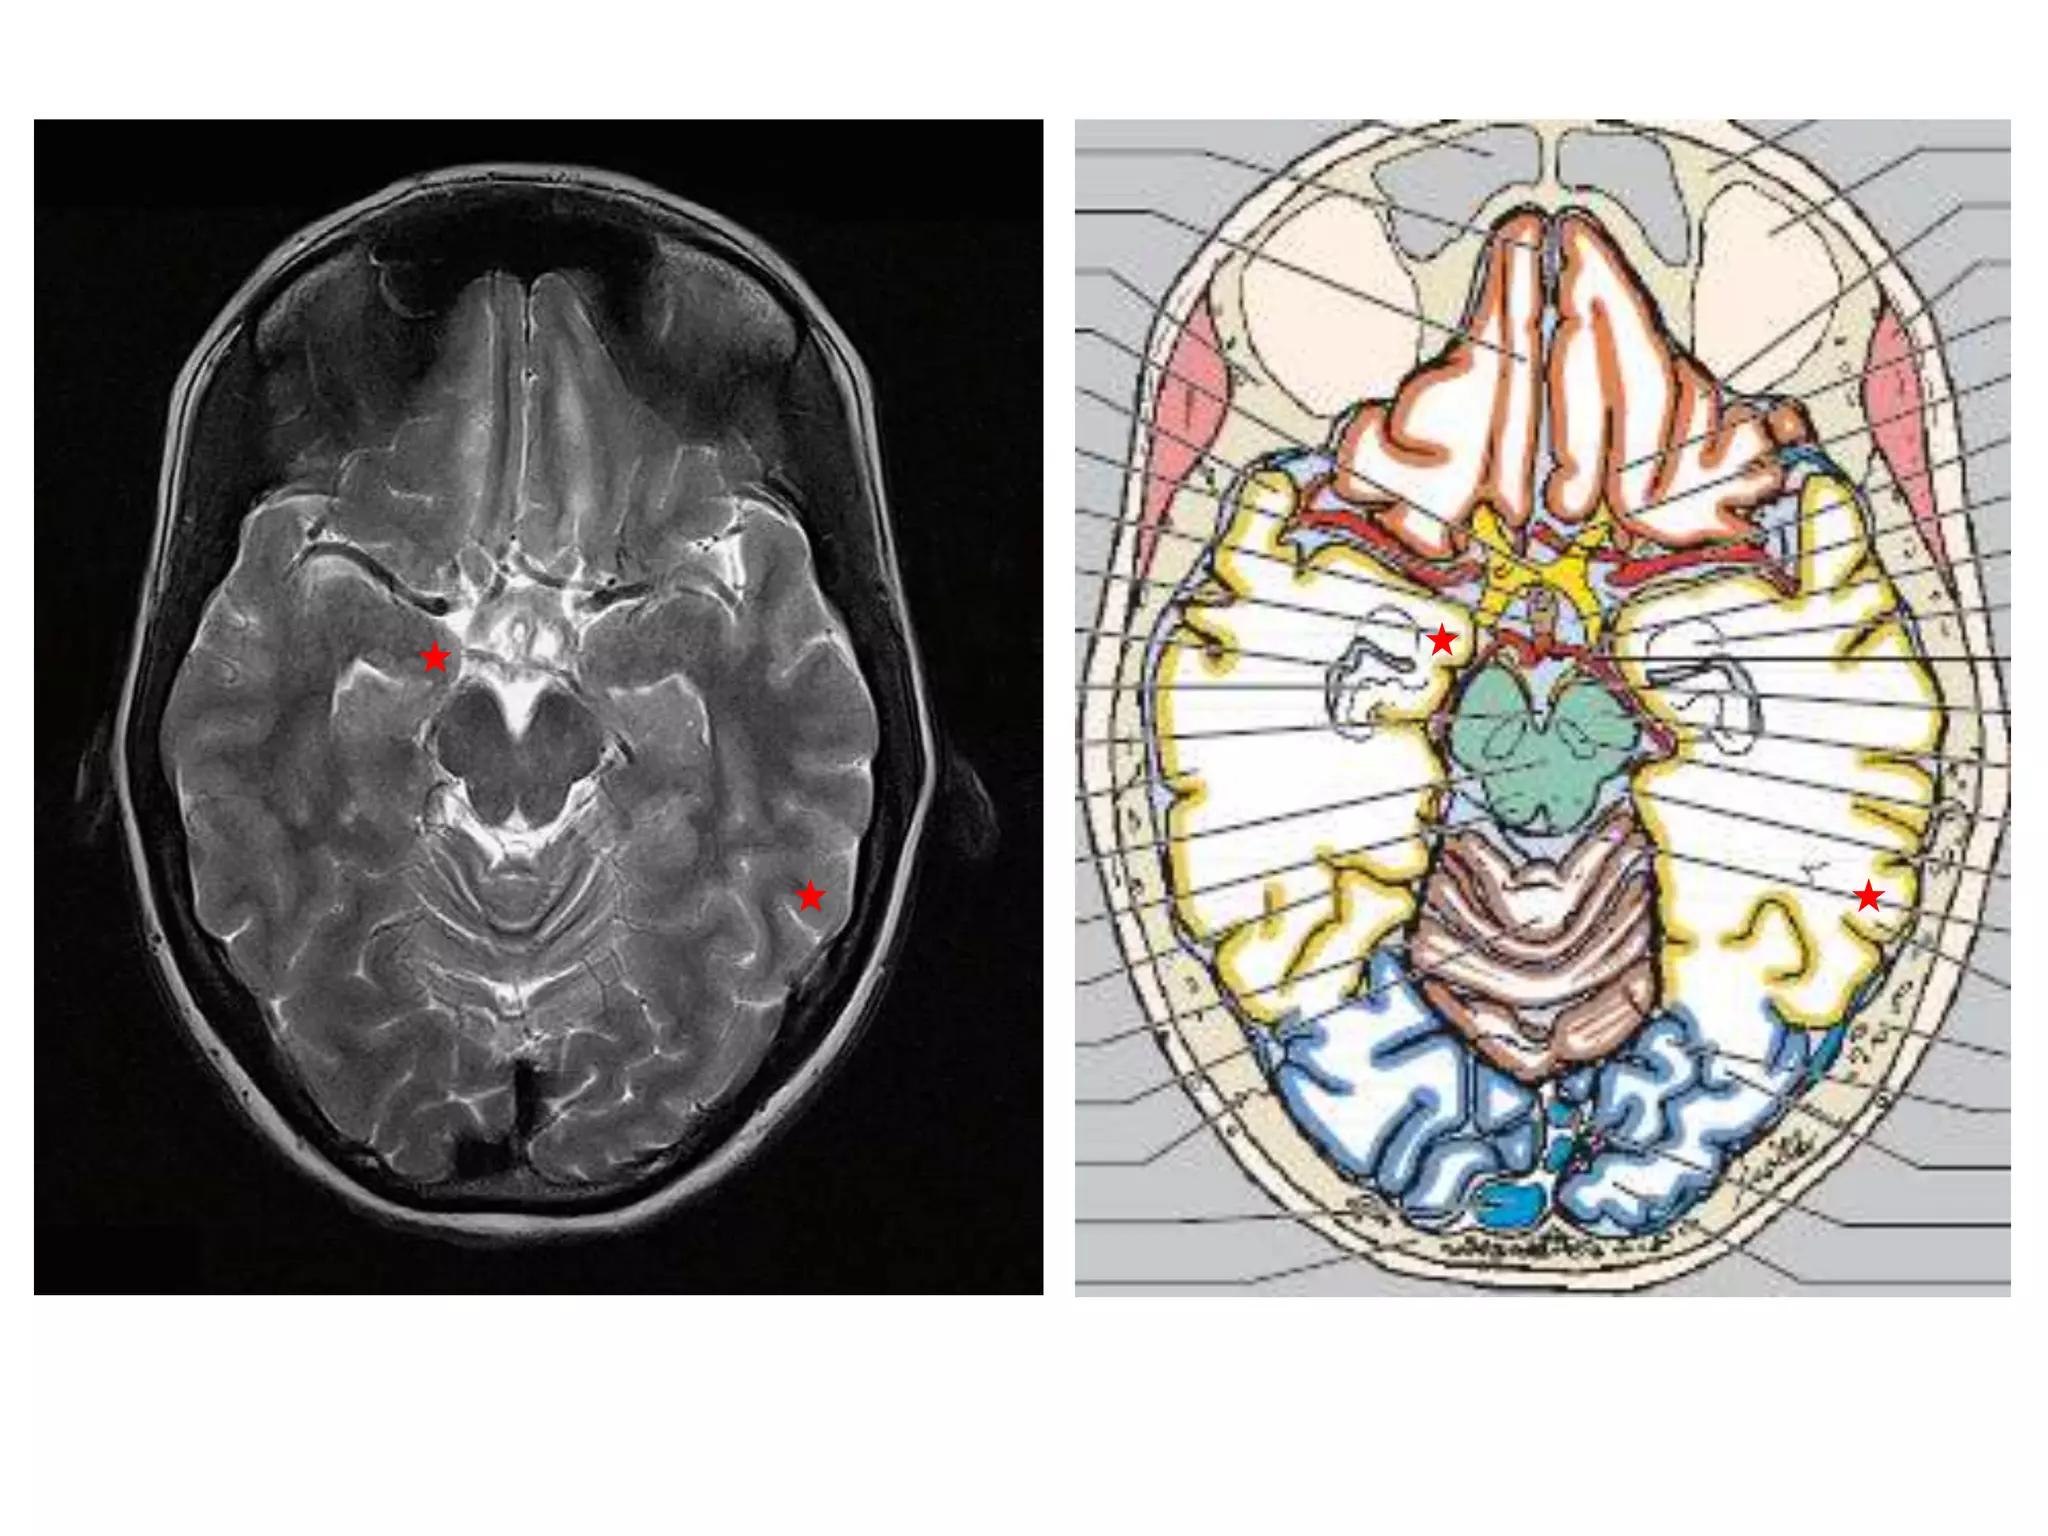

Radiology

• Axial MRI / CT – ‘kidney bean’ turned on its side.

• Saggital MRI - mid point of line drawn b/w T. sella

and trocula should intersect middle of 4th

ventricle.

• Coronal MRI – elongated rhomboid shape

CISTERNS

• Where brain and skull are not closely

apposed, arachnoid and pia separate – and form

cisterns .

• Mainly present at base of brain, around brain stem and

free edge of tentorium.

1.   Posterior fossa cisterns

2.   Basal cisterns

3.   Mesencephalic cisterns

4.   Lateral superior cisterns